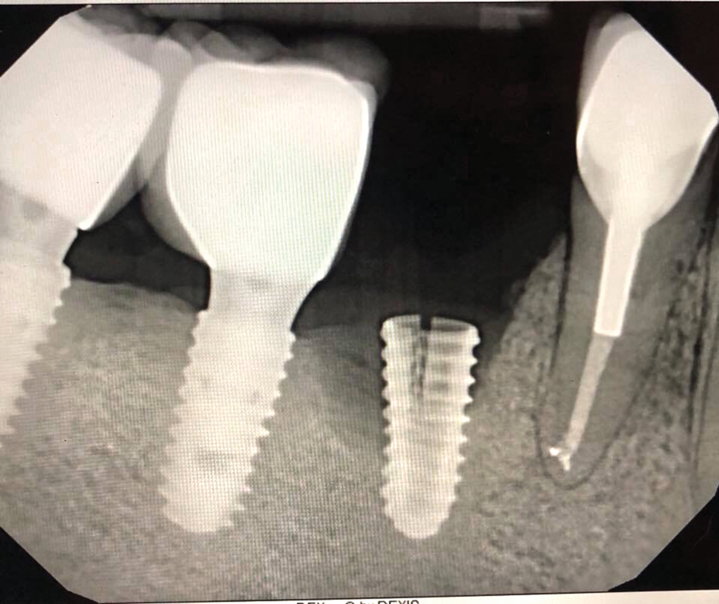

Implants with internal hex connections are more prone to failure at the connection than those with external hex connections.28 This is related to the thickness of the metal at the thinnest point between the internal surface of the interface and the external surface at the crestal area of the implant. When overloaded, implants with an internal hex connection may present with fractures at the points of the hex.29 These points are where the metal is the thinnest at the crestal portion of the implant and where stress is concentrated during overloading. This is less problematic in wider diameter implants because the metal is thicker in this area of the implant; however, in standard or narrow diameter implants, fracture may result, causing catastrophic failure of the implant (Figure 1). This may also occur in other internal implant connection types, such as trilobe connections, especially when the crestal thickness of the implant is minimal, leading to fracture of the coronal aspect of the implant (Figure 2). Implants with conical connections are not immune to potential fracture in this area, and the thin walls of some standard or narrow diameter models may split even without the isolated stress points observed in internal hex-, trilobe-, and octagon-type connections (Figure 3).30 Sometimes, fractures of implants at the coronal aspect are not clinically visible but, instead, are identified radiographically either after a patient complaint of pain in the area, due to the presence of soft-tissue inflammation, or during a routine examination with no patient complaint (Figure 4).

Coronal implant fracture, whether it is incomplete (Figure 5) or involves a visible loss of a portion of the implant platform (Figure 6 and Figure 7), results in catastrophic failure of the implant. The presence of any fracture in the coronal aspect of an implant necessitates explantation. These implants cannot be salvaged because an incomplete fracture will continue to propagate due to micromovement of the abutment and implant at the connection during function. Off-axis loads are amplified when there is a longer distance between the implant's platform and the most coronal surface of the restoration because the fulcrum arm is increased, allowing higher loading forces at the platform.31

(3.) An implant with a conical connection demonstrating fracture of the thin walls at the coronal aspect (Radiograph courtesy of Ramsey Amin, DDS).

Figure 3